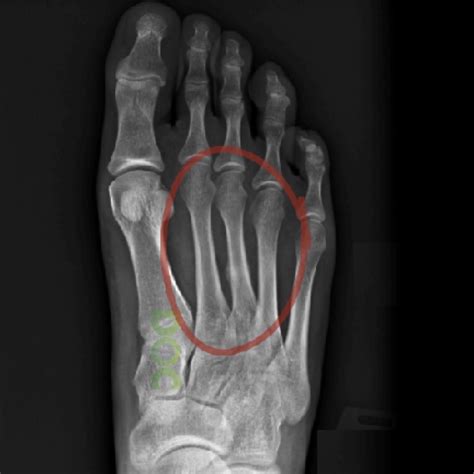

Anatomy of a foot showing common stress fracture locations

Location Often in the metatarsals (bones of the midfoot) or calcaneus (heel)